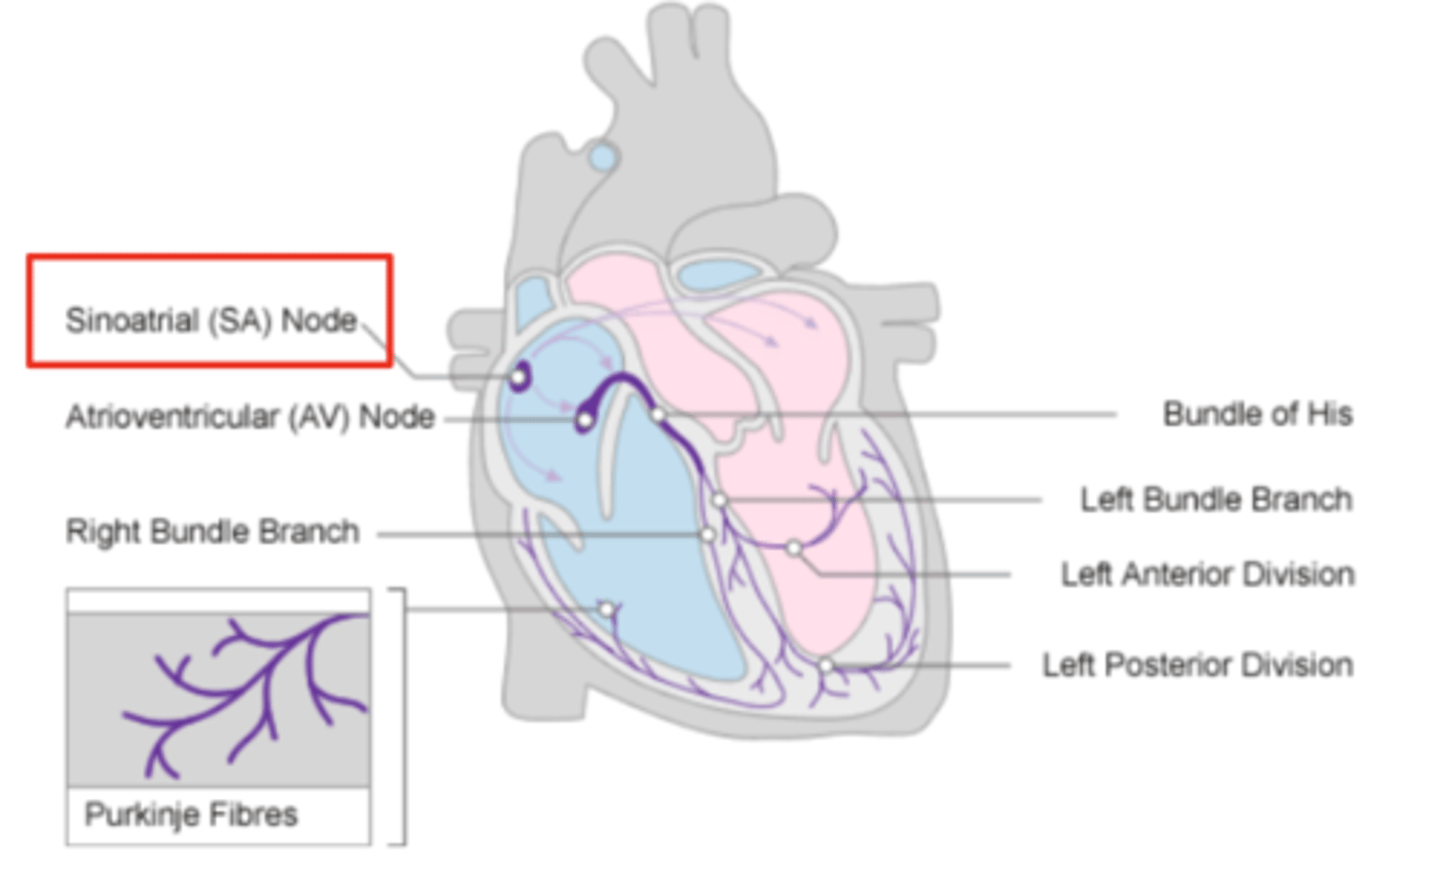

What allows the heart to contract by itself?

The heart possesses a specialized conduction system that gives it the autonomous capacity to contract, allowing it to pump by itself in a correct buffer.

What are the two conduction nodes of the heart conduction system?

. SA node (sinoatrial node)

. AV node (atrioventicular node)

What is the function of the sinoatrial (SA) node?

Pacemaker of the heart

Where is initiated the contraction of the SA node?

SVC (Superior Vena Cava)

passing through the atrium to the AV node

Where is the SA located?

upper wall of the right atrium,

at the junction where the superior vena cava enters

Where is the atrioventricular (AV) node located, and what follows it?

At the level of the atrioventricular septum,

AV node is followed by?

Bundle of Hiss that divides into two branches

Where does Bundle of Hiss ends?

Purkninje fibers

Describe the propagation of waves in the conduction system ?

. SA node sends the initial wave

Passes through the walls of the atria

. Ends at the AV node in the AV septum

. Travels along the Bundle of His

. Reaches Purkinje fibers in the walls of the ventricles

What role does the moderator band play in the conduction system?

Allows the wave to reach the papillary muscles, inducing their contraction simultaneously with that of the ventricles.

REMEMBER: PAPILLARY MUSCLES ACT THROUGH THE CHORDAE TENDINAE TO CONTROL THE TRICUSPID AND MITRAL VALVES.

What is the significance of the Bundle of His in heart conduction?

Branching to the right and left to ensure coordinated contraction of the ventricles.

What are the Purkinje fibers, and what is their function?

specialized conductive fibers in the walls of the ventricles that

facilitate rapid transmission of electrical impulses,

ensuring efficient and synchronized ventricular contraction.

How does the AV node contribute to heart rhythm?

Delays the electrical impulse from the SA node,

ensuring that the atria contract fully to transfer blood to the

ventricles before the ventricles contract.